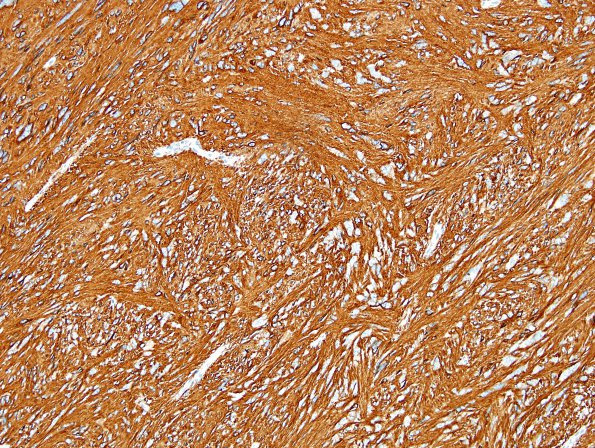

2B1,2 The tumor is strongly and diffusely GFAP positive. The histomorphologic appearance and immunohistochemical profile of this lesion are those of an ependymoma, tanycytic variant. The numerous enlarged, pleomorphic cells are likely a degenerative change.